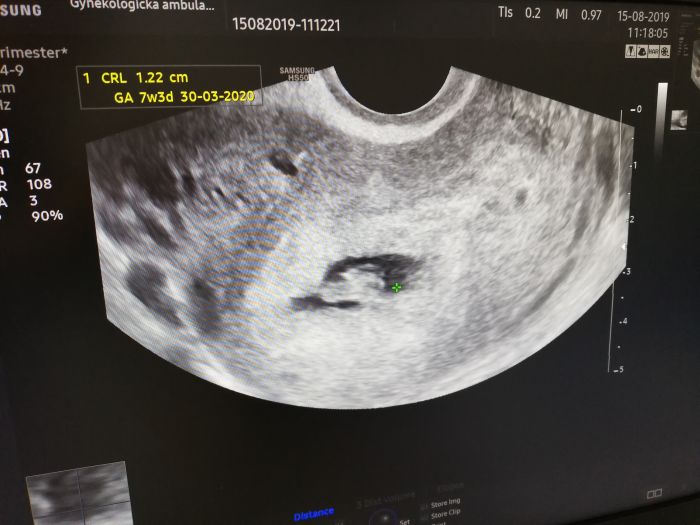

Krásná fotečka